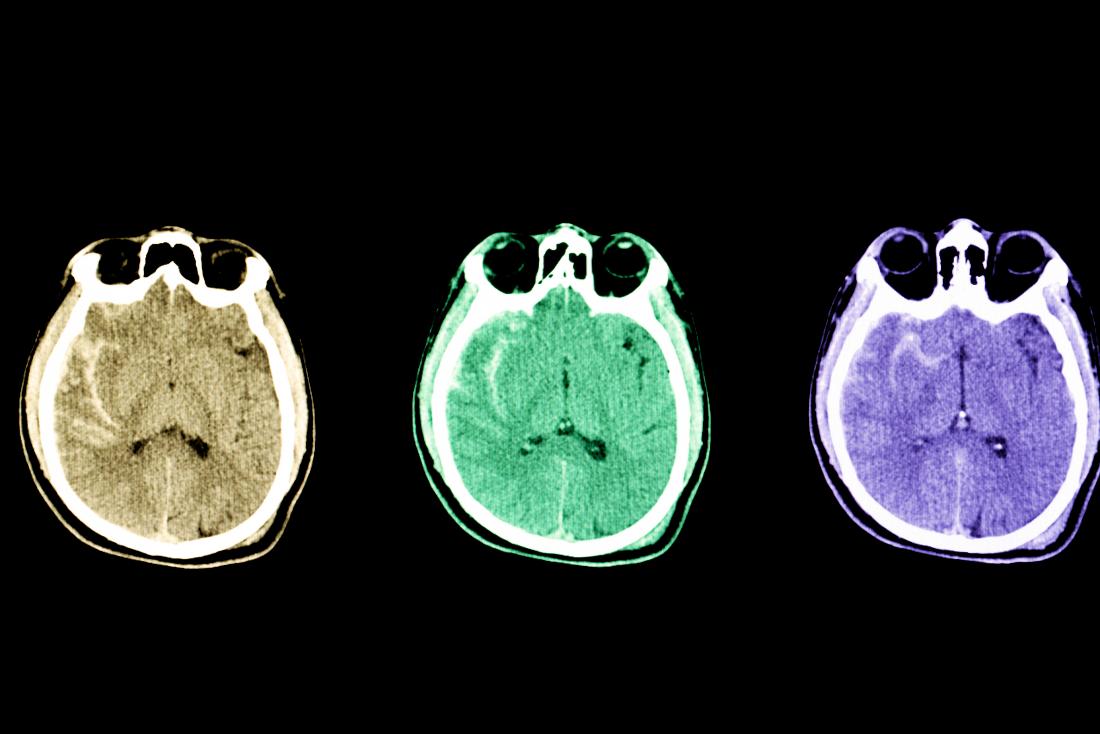

Υπολογιστική τομογραφία (ΥΤ) ή Μαγνητική τομογραφία:

- Η διάγνωση είναι δυνατή σε περισσότερες από 95% των περιπτώσεων με την ΥΤ. Αυτή αναδεικνύει την ύπαρξη αίματος στις μεσοσκελιαίες δεξαμενές και μπορεί να βοηθήσει στον εντοπισμό της εστίας της αιμορραγίας

- Μπορεί επίσης να αποκλείσει την ύπαρξη όγκου ώστε όταν η εξέταση είναι αρνητική να μπορεί επιτελεσθεί μία οσφυονωτιαία παρακέντηση με ασφάλεια

- Ένα μικρό ποσοστό υπαραχνοειδών αιμορραγιών δε γίνεται αντιληπτό από τη ΥΤ